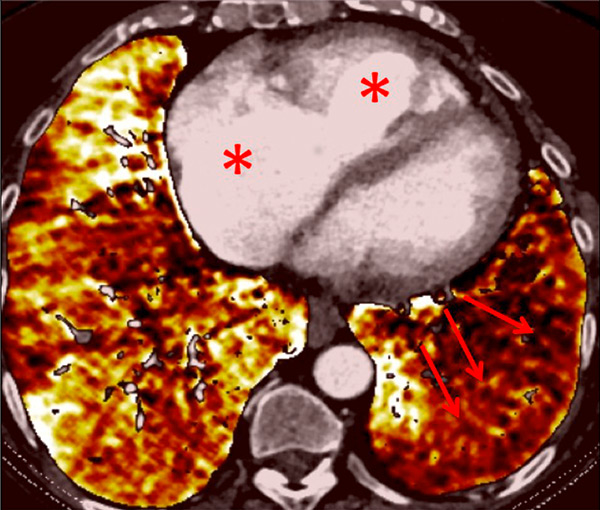

Figure 10

Severe bronchopathy (arrow) in the left lower lobe (A) associated with extended hypoperfusion (arrow) and dilatation of the right cardiac cavities (stars) (B).